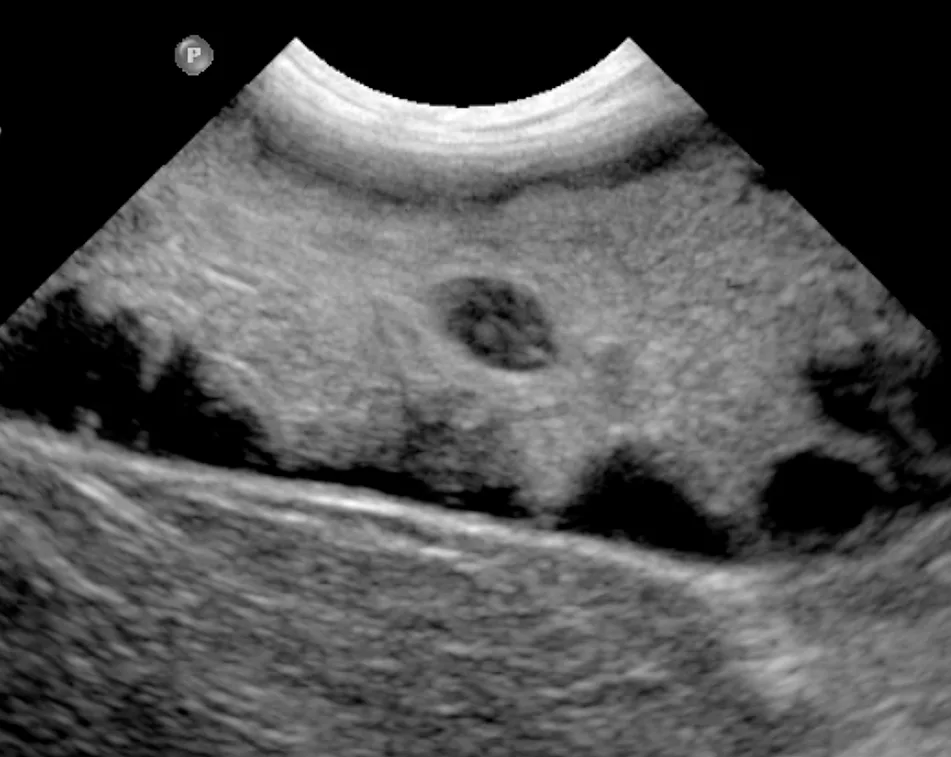

Ultrasonographic image of a GBM displaying a stellate pattern

Abdominal ultrasonography is key to diagnosis of GBMs. The classic description of GBMs is a kiwi-like appearance of intraluminal gallbladder contents with hyperechoic immobile striations of inspissated bile in hypoechoic mucus structures (Figure 1). Other ultrasonographic appearances of GBMs include echogenic immobile biliary sludge filling the gallbladder or a stellate pattern (Figure 2).6,10,11 These different GBM appearances on ultrasonographic images likely represent a continuum of early to mature mucoceles.6 Ultrasonography cannot be used alone to determine the clinical significance of GBMs or guide treatment decisions unless there is clear evidence of biliary rupture or obstruction that warrants urgent surgical intervention (see Gallbladder Rupture).1,3,10